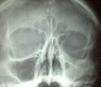

Se le realizaron estudios radiográficos simples en los que se observó una opacidad en el seno maxilar derecho, razón por la cual se realizó un estudio tomográfico, en el que se encontró un aumento leve del volumen orbitario, junto con un seno maxilar atelectásico opaco, con una isodensidad a tejidos blandos en su interior (fig. 1).